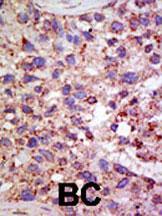

Supportive validation

- Submitted by

- Abcepta (provider)

- Main image

- Experimental details

- "Formalin-fixed and paraffin-embedded human cancer tissue reacted with the primary antibody, which was peroxidase-conjugated to the secondary antibody, followed by AEC staining. This data demonstrates the use of this antibody for immunohistochemistry; clinical relevance has not been evaluated. BC = breast carcinoma; HC = hepatocarcinoma."

- Primary Ab dilution

- 1:50~100